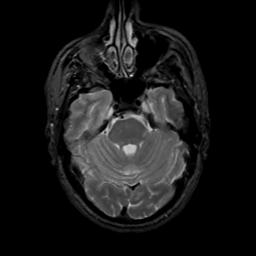

MR Study #7, March 24, 1991 -- Slice #14